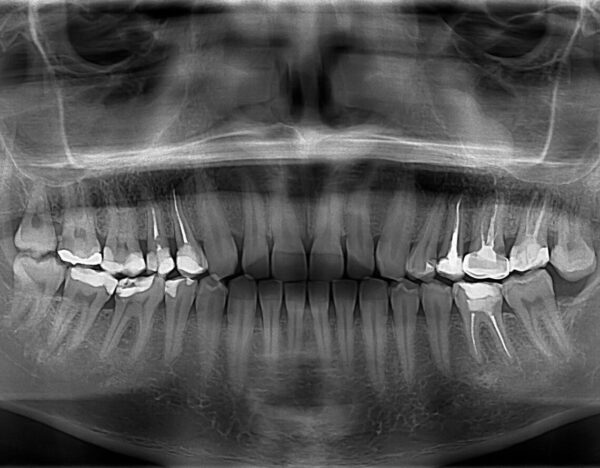

Dental X-rays are a type of imaging that allows us to view your teeth, gums, and jawbone in great detail. Using a small dose of radiation, these images help us see areas we can’t inspect with the naked eye, including between teeth, under the gums, and within the bone. They are a safe and effective tool that gives us valuable insights into your overall oral health.

- Early Detection of Problems: Dental X-rays allow us to catch issues like tooth decay, gum disease, and infections before they become more serious, helping you avoid costly and extensive treatments in the future.

- Accurate Diagnosis: X-rays give us a complete picture of your oral health, ensuring that we can develop a treatment plan that’s tailored to your specific needs.

- Safe and Efficient: Modern digital X-rays minimize radiation exposure while providing high-quality images in a matter of seconds.